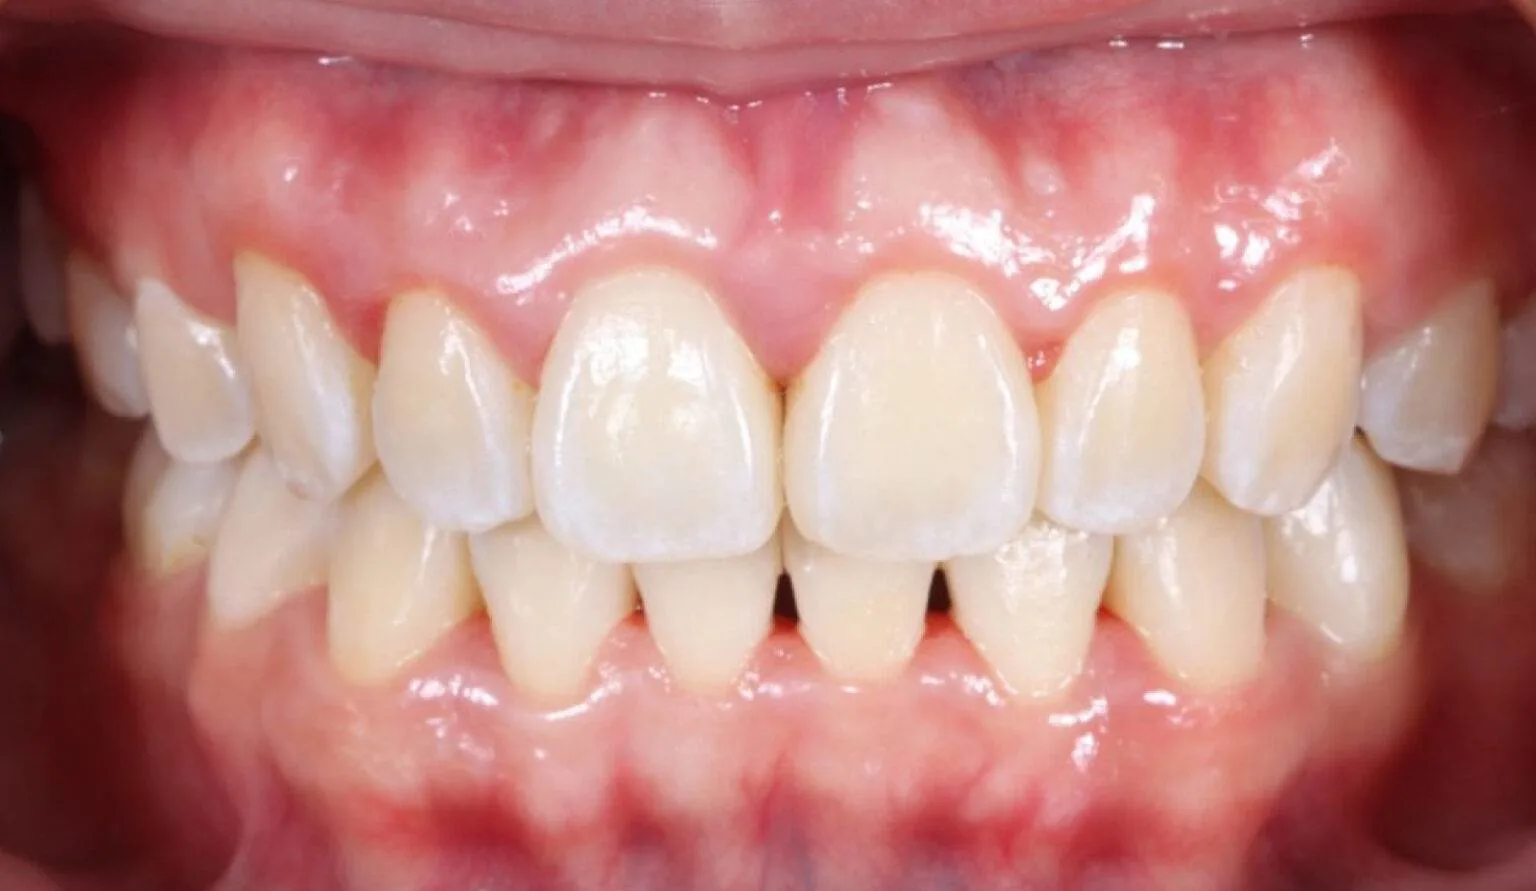

Before & After Invisalign® Gallery